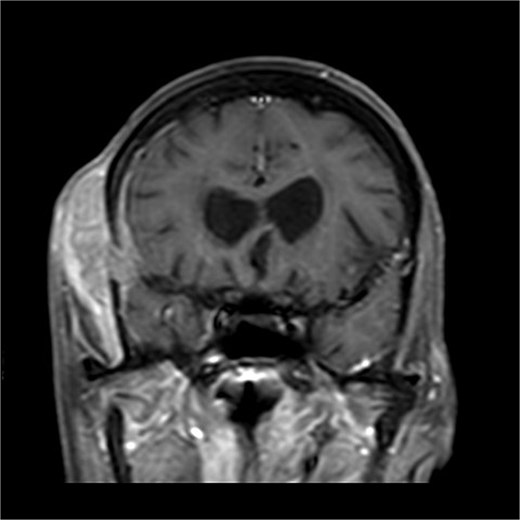

A 70-years old female came to the tertiary hospital, with a gradually enlarging right frontal-temporal scalp swelling associated with headache. She presented to the ER with abnormal movement, described by the son was gazing upward toward specific point with right upper limb jerky movement lasting for 15 s and frothy secretions, not responding during the event. Whole event lasted for 40–45 s. No reported pre-event symptoms and for post event patient was back to baseline after one-to-one hour and half. The son noticed this event repetitively happens on exertion, positioning the patient from lying to siting position, and before the dialysis sessions. Regarding her surgical and medical history, she is a known case of type 2 diabetes mellitus, hypertension, end-stage renal disease on dialysis, and cardiac disease with low ejection fraction. In addition, the patient had undergone a total abdominal hysterectomy with bilateral salpingo-oophorectomy under spinal anaesthesia in for endometria carcinoma, stage IB, grade 2 and subsequently received vaginal vault brachytherapy. Upon physical examination, the patient was noted to have a large, non-tender, soft to firm swelling in the right frontal-temporal region, with no other remarkable findings. CT with contrast (Figs 1 and 2) of the brain revealed metastasis to the right frontal bone and the greater wing of the sphenoid, with large extra-cranial and small intracranial soft tissue components with no parenchymal brain lesions were observed. A brain biopsy confirmed that there was fibromuscular and adipose tissue with focal necrosis and atypical cells, with crushed and scarse atypical cells likely neoplastic or reactive. Also, PET CT scan (Figs 3 and 4) confirms that there was brain metastasis sparing lymph nodes. Given her poor status and significant comorbidities, she was deemed unfit for systemic chemotherapy. The patient received palliative radiotherapy to the scalp lesion 20 Gy in 5 fractions.

There is a bone lesion involving the right frontal bone and, to a lesser extent, the right greater wing of the sphenoid, with a sizable extracranial soft tissue component in the temporal fossa measuring 5 × 1.8 × 5.4 cm in CC, TV, and AP dimensions respectively. There is also a small related intracranial extra-axial soft tissue component with associated pachymeningeal mild thickening and enhancement over the frontotemporal cerebral convexity. No obvious brain parenchymal invasion is noted, No midline shift or brain herniation. There is generalized brain tissue volume loss in the form of prominence of sulci, gyri, and ventricular system. A tiny focus of blooming effect is noted at the right cerebellar hemisphere.